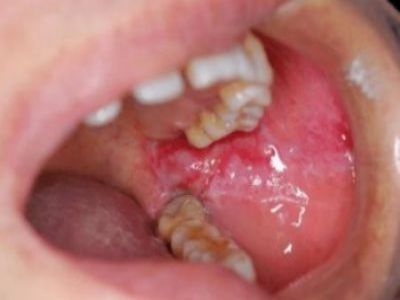

唇内侧

溃疡

创伤性溃疡口腔黏膜上有一块红溃疡图

创伤性溃疡是因长期刺激所引发,唇内侧黏膜发红,靠近牙齿部位有数个白色小溃疡,持续刺激后创面会出现炎性增生,若未继发感染,解除刺激后可较快愈合。